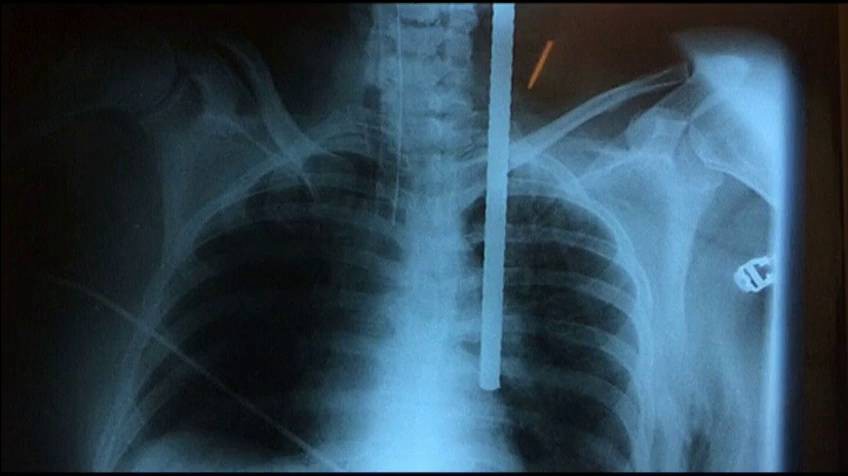

Al impactar contra el suelo, la mujer se clavó un hierro que le entró por la clavícula y llegó hasta el pulmón.

En el hospital los médicos observaron que la barra de metal le ingresó al cuerpo y quedó a milímetros de la arteria aorta.